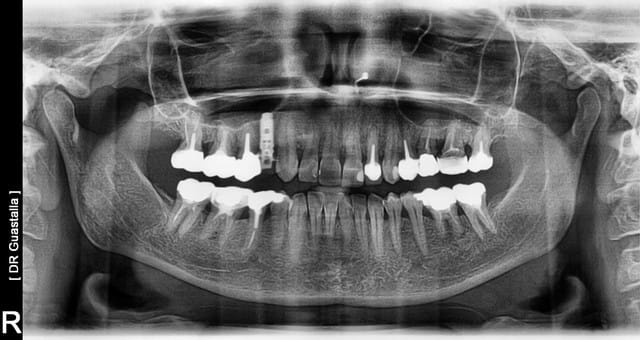

Ci-joint un p'tit cas adressé suite endo pour douleur...

fellure ? je pensais résorption interne...et bien perforations bi-lattérales, racine avec double dépressions.

L'alvéole est pas bonne pour un implant...

En plus, le sinus est visible au fond de l'alvéole, suite au curetage du ciment en apex...j'aurais pas été en mesure de placer plus long pour stabilisation...

voir photo montage...direct dans le sinus...